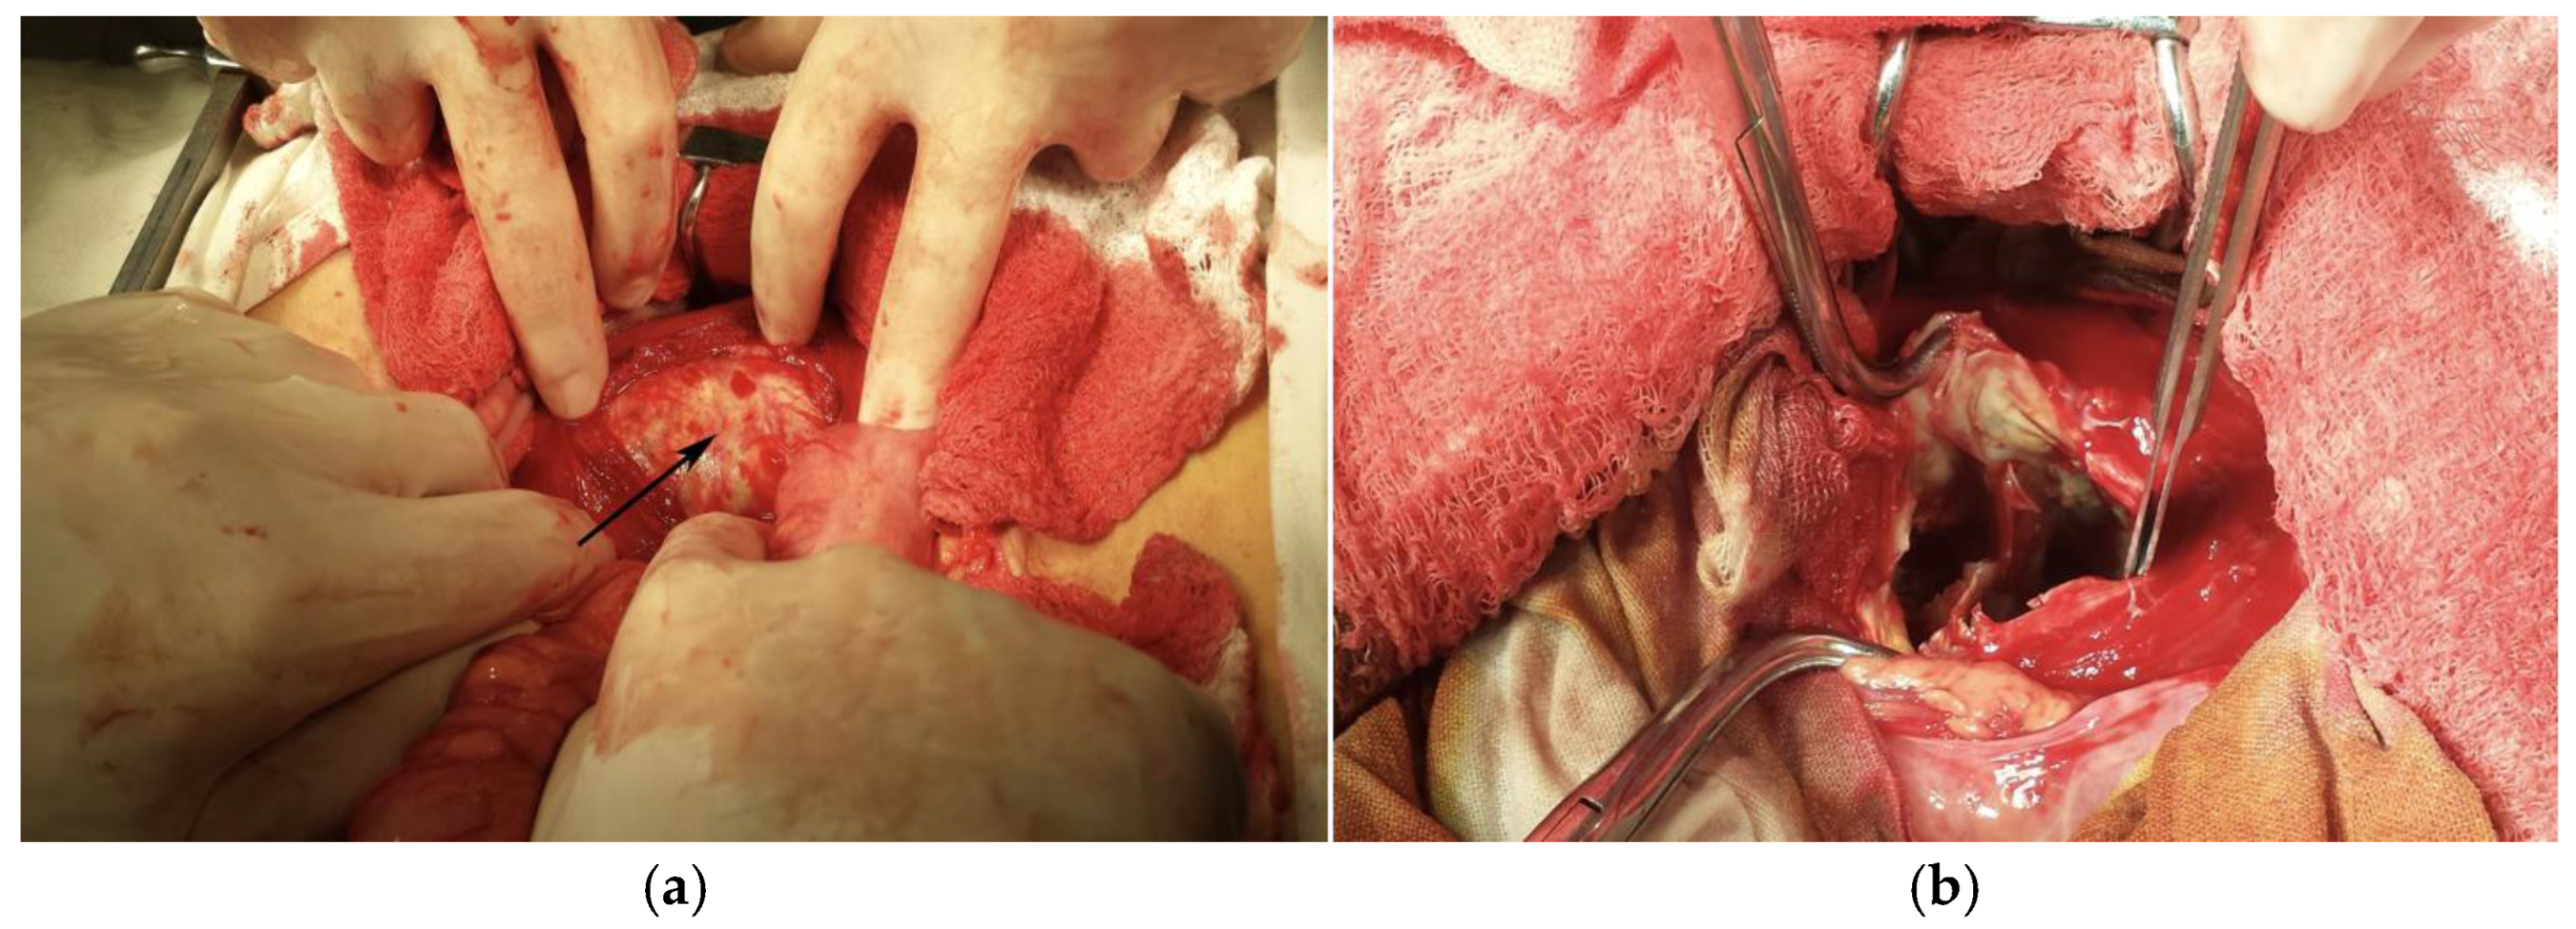

| 2020 | Yassine Merad [21] | Algeria | 16-year-old female, no pathological history | Right flank pain, a few episodes of vomiting in the previous 3 days | Positive | AUS CT | Pericystectomy + Albendazole 2 × 400 mg/day for 3 months |